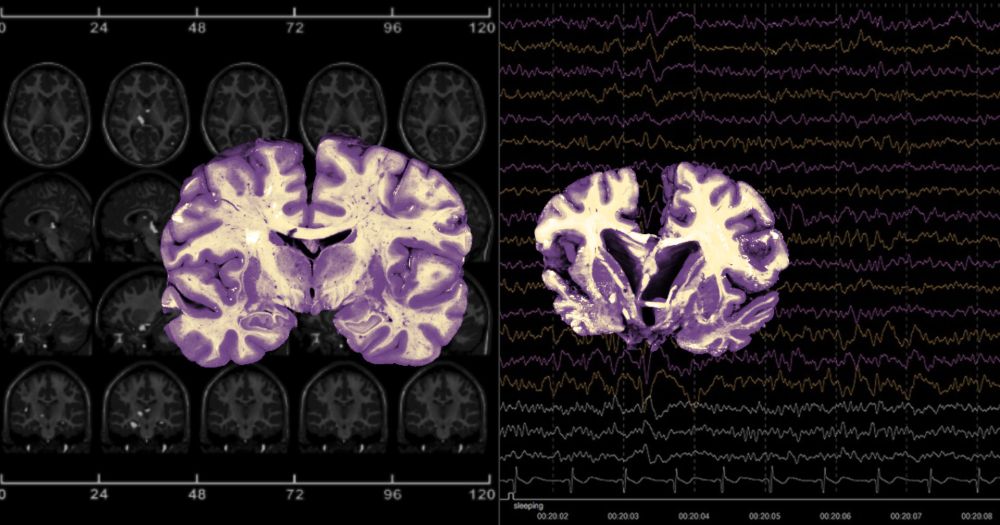

Estudo revela que mais de 50% dos casos de demência na América Latina são evitáveis Pesquisa recomenda que intervenções preventivas sejam feitas com urgência, com promoção de mudanças no estilo de vida e acesso a tratamentos médicos

Estudo revela que mais de 50% dos casos de demência na América Latina são evitáveis

Pesquisa recomenda que intervenções preventivas sejam feitas com urgência, com promoção de mudanças no estilo de vida e acesso a tratamentos médicos